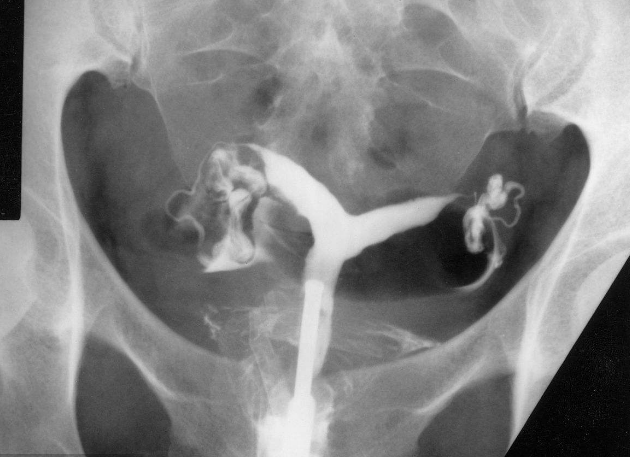

相關檢查:

子宮輸卵管造影

雙角子宮圖片